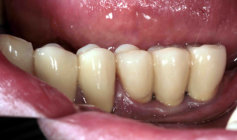

Situation vorher (Brückenanhänger,

abnehmbar mit Geschiebe, ist bereits

entfernt)